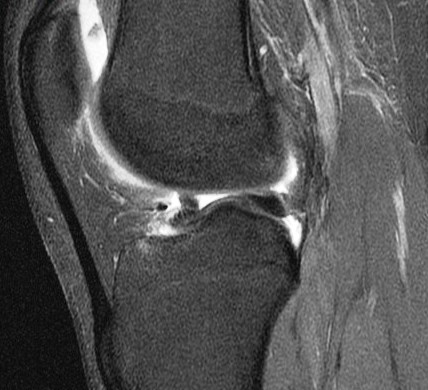

Figure 3 for case Unstable displaced lateral meniscus flap tear( RID2763 )

Figure 3

The flap is folded and displaced into the notch.

Unstable displaced lateral meniscus flap tear( RID2763 )